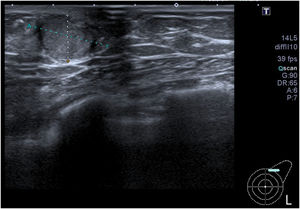

Se completó el estudio diagnóstico realizándose mamografía y ecografía (fig. 1) de ambas mamas con los siguientes hallazgos: nódulo sólido BIRADS 5 en la mama izquierda de 2 x 1,5 cm (fig. 2), adenopatías axilares Bedi 1 y ginecomastia derecha.